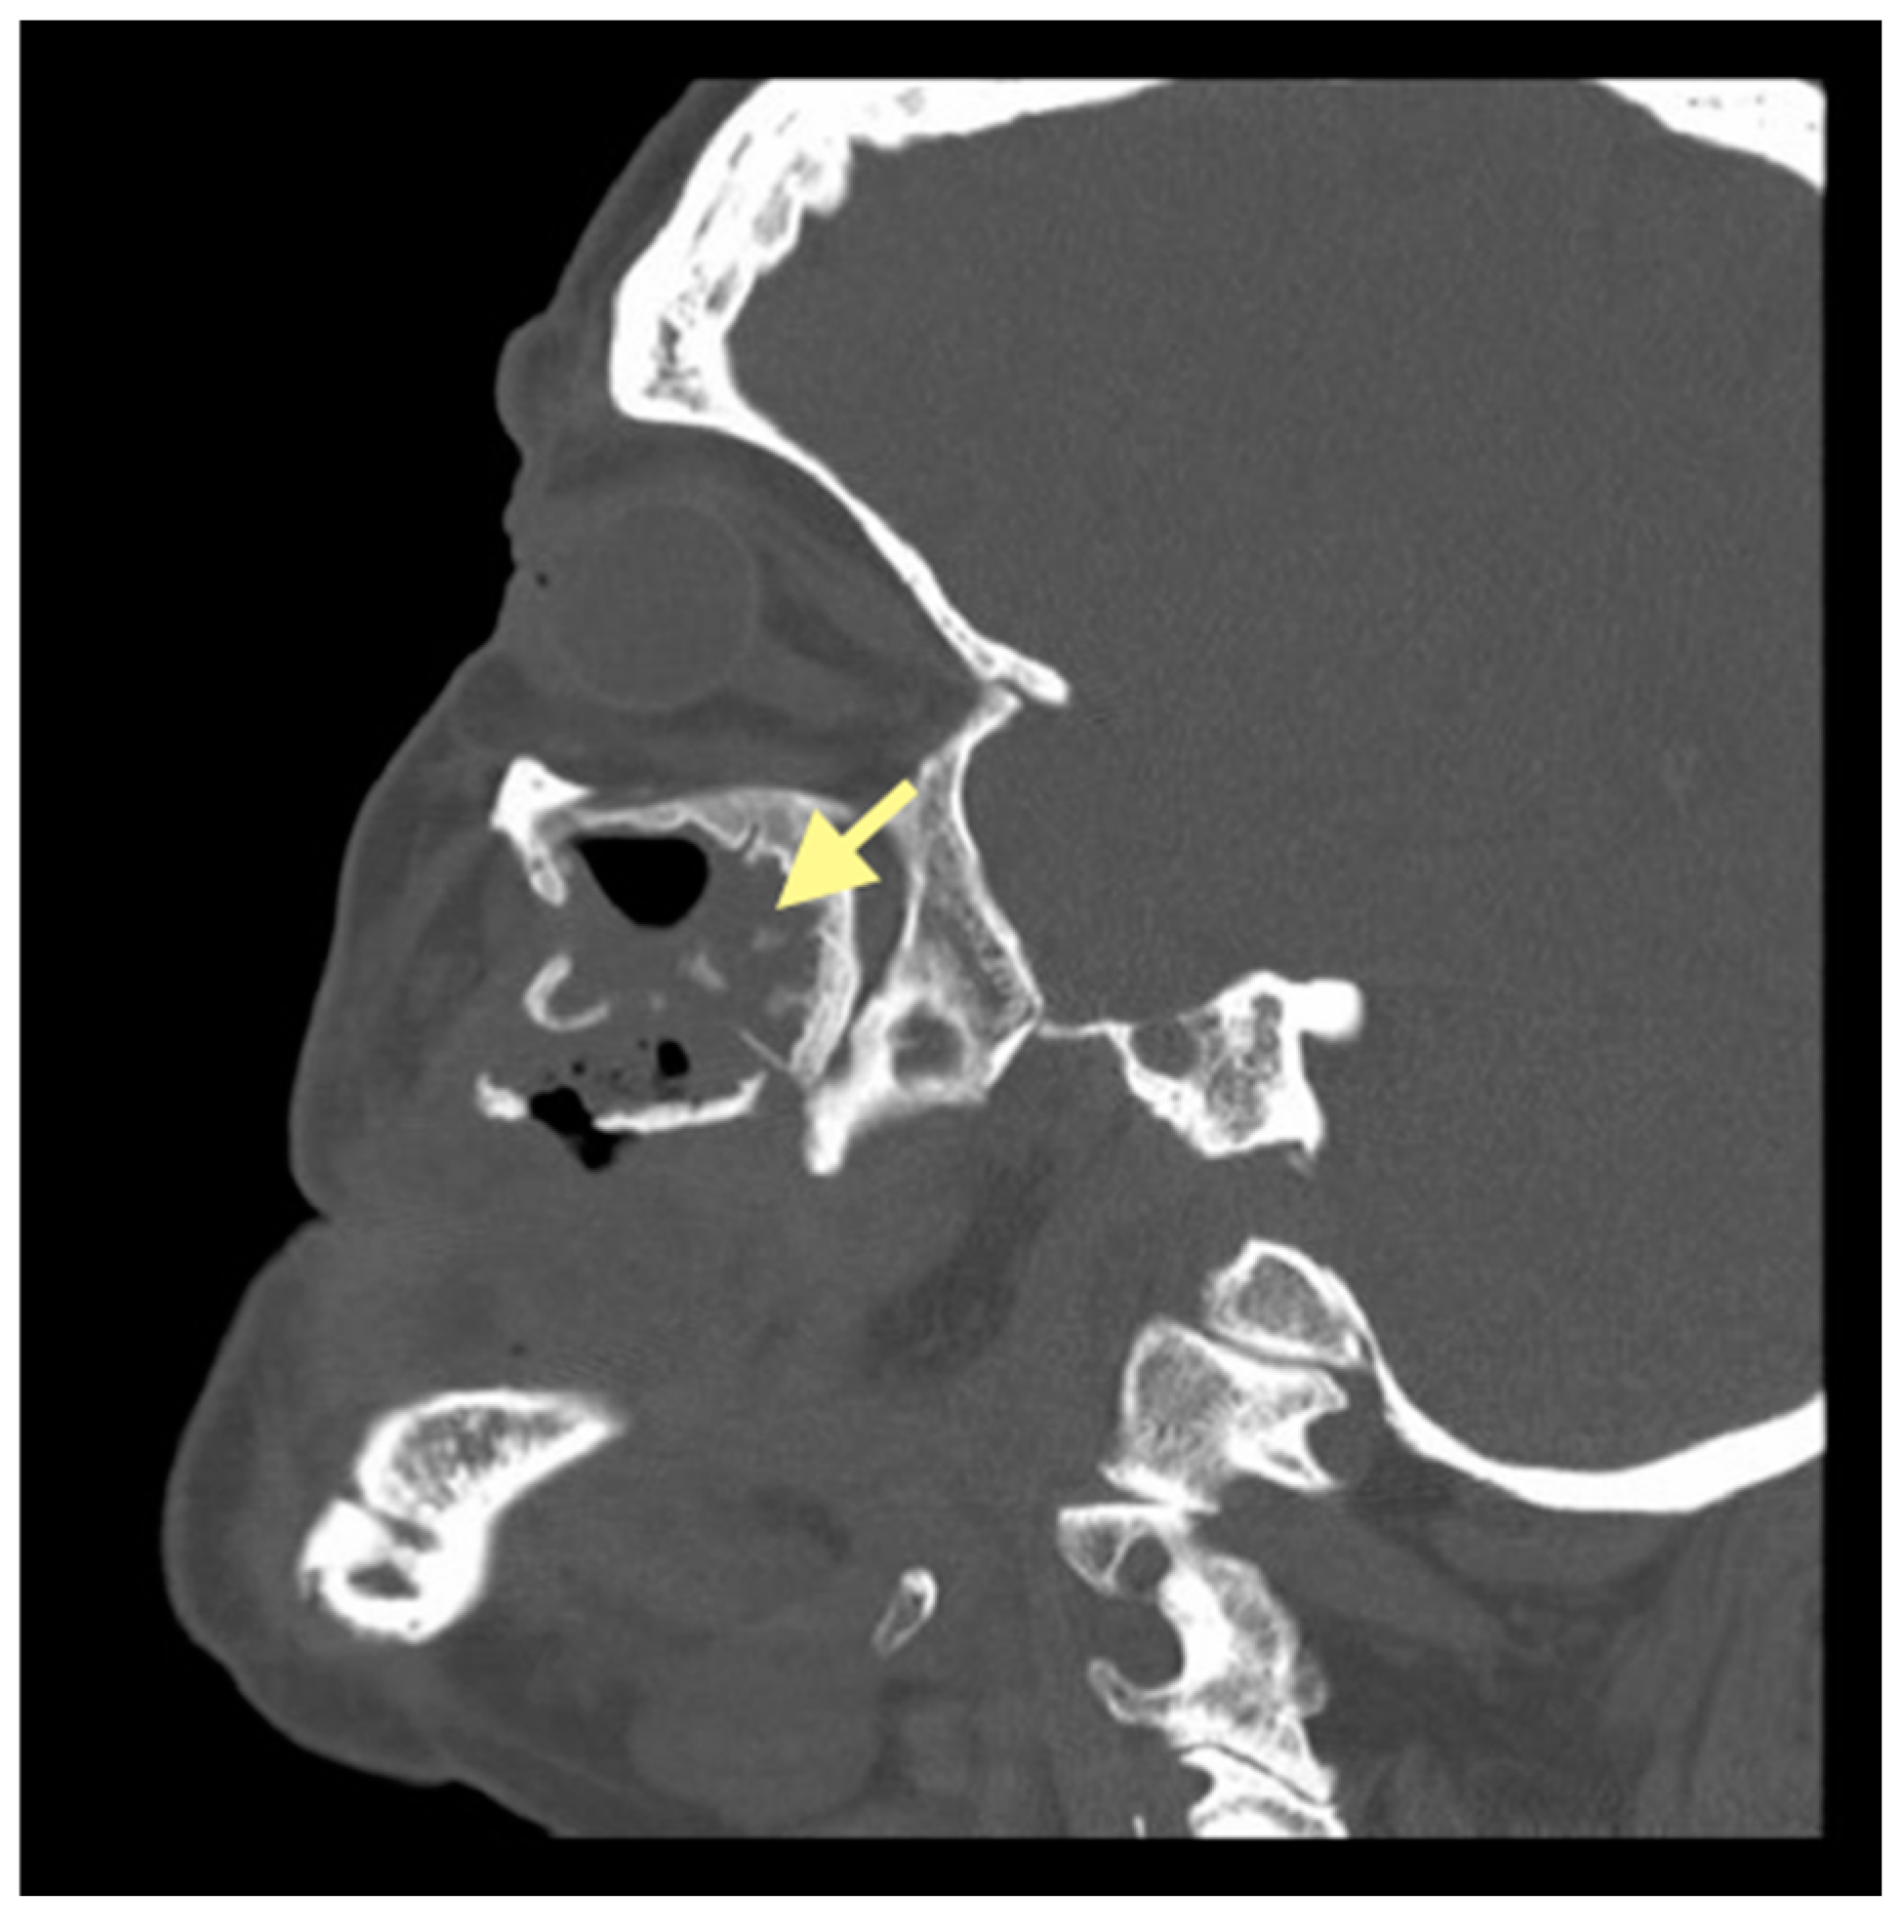

Figure 7.

CT of the head and facial bones (16 December 2024).

The third patient was a 75-year-old female with osteonecrosis of the mandible and maxilla in the fourth and in the second quadrant (see Figure 7, Figure 8 and Figure 9). The patient had third-stage jaw osteonecrosis. In 2023, the patient was diagnosed with osteonecrosis of the upper and lower jaw caused by antiresorptive therapy (until August 2021, the patient regularly used Zolendronic acid; then, this drug was replaced by the RANKL inhibitor Denosumab). The treatment was periodically complicated by submandibular and submental abscesses. In addition, due to the progression of the underlying disease, constant courses in chemotherapy were administered. The patient underwent three operations, which included sequestrectomy of the jaw with simultaneous use of A-PRF, antrotomy with revision of the maxillary sinus, closure of the oroantral communication, and opening and revision of abscesses of the soft tissues (see Figure 10 and Figure 11)